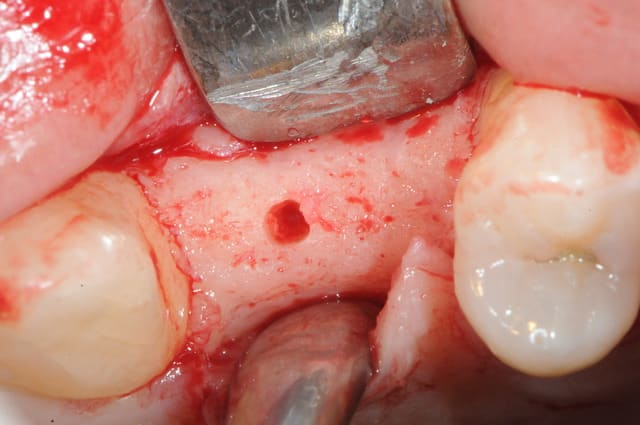

dis moi la tu le trouves comment mon compromis avec l'espace biologique

eii

d'après toi faites il y a combien de temps?

Superbe ratrapage suite à une operculisation d'une vis de couverture. Félicitations. Je te savais costaud béotien mais là tu m'impressionnes vraiment.

- pas de vis de couverture , pas d'operculisation!!

Même pas de lambeau pédiculé palatin!